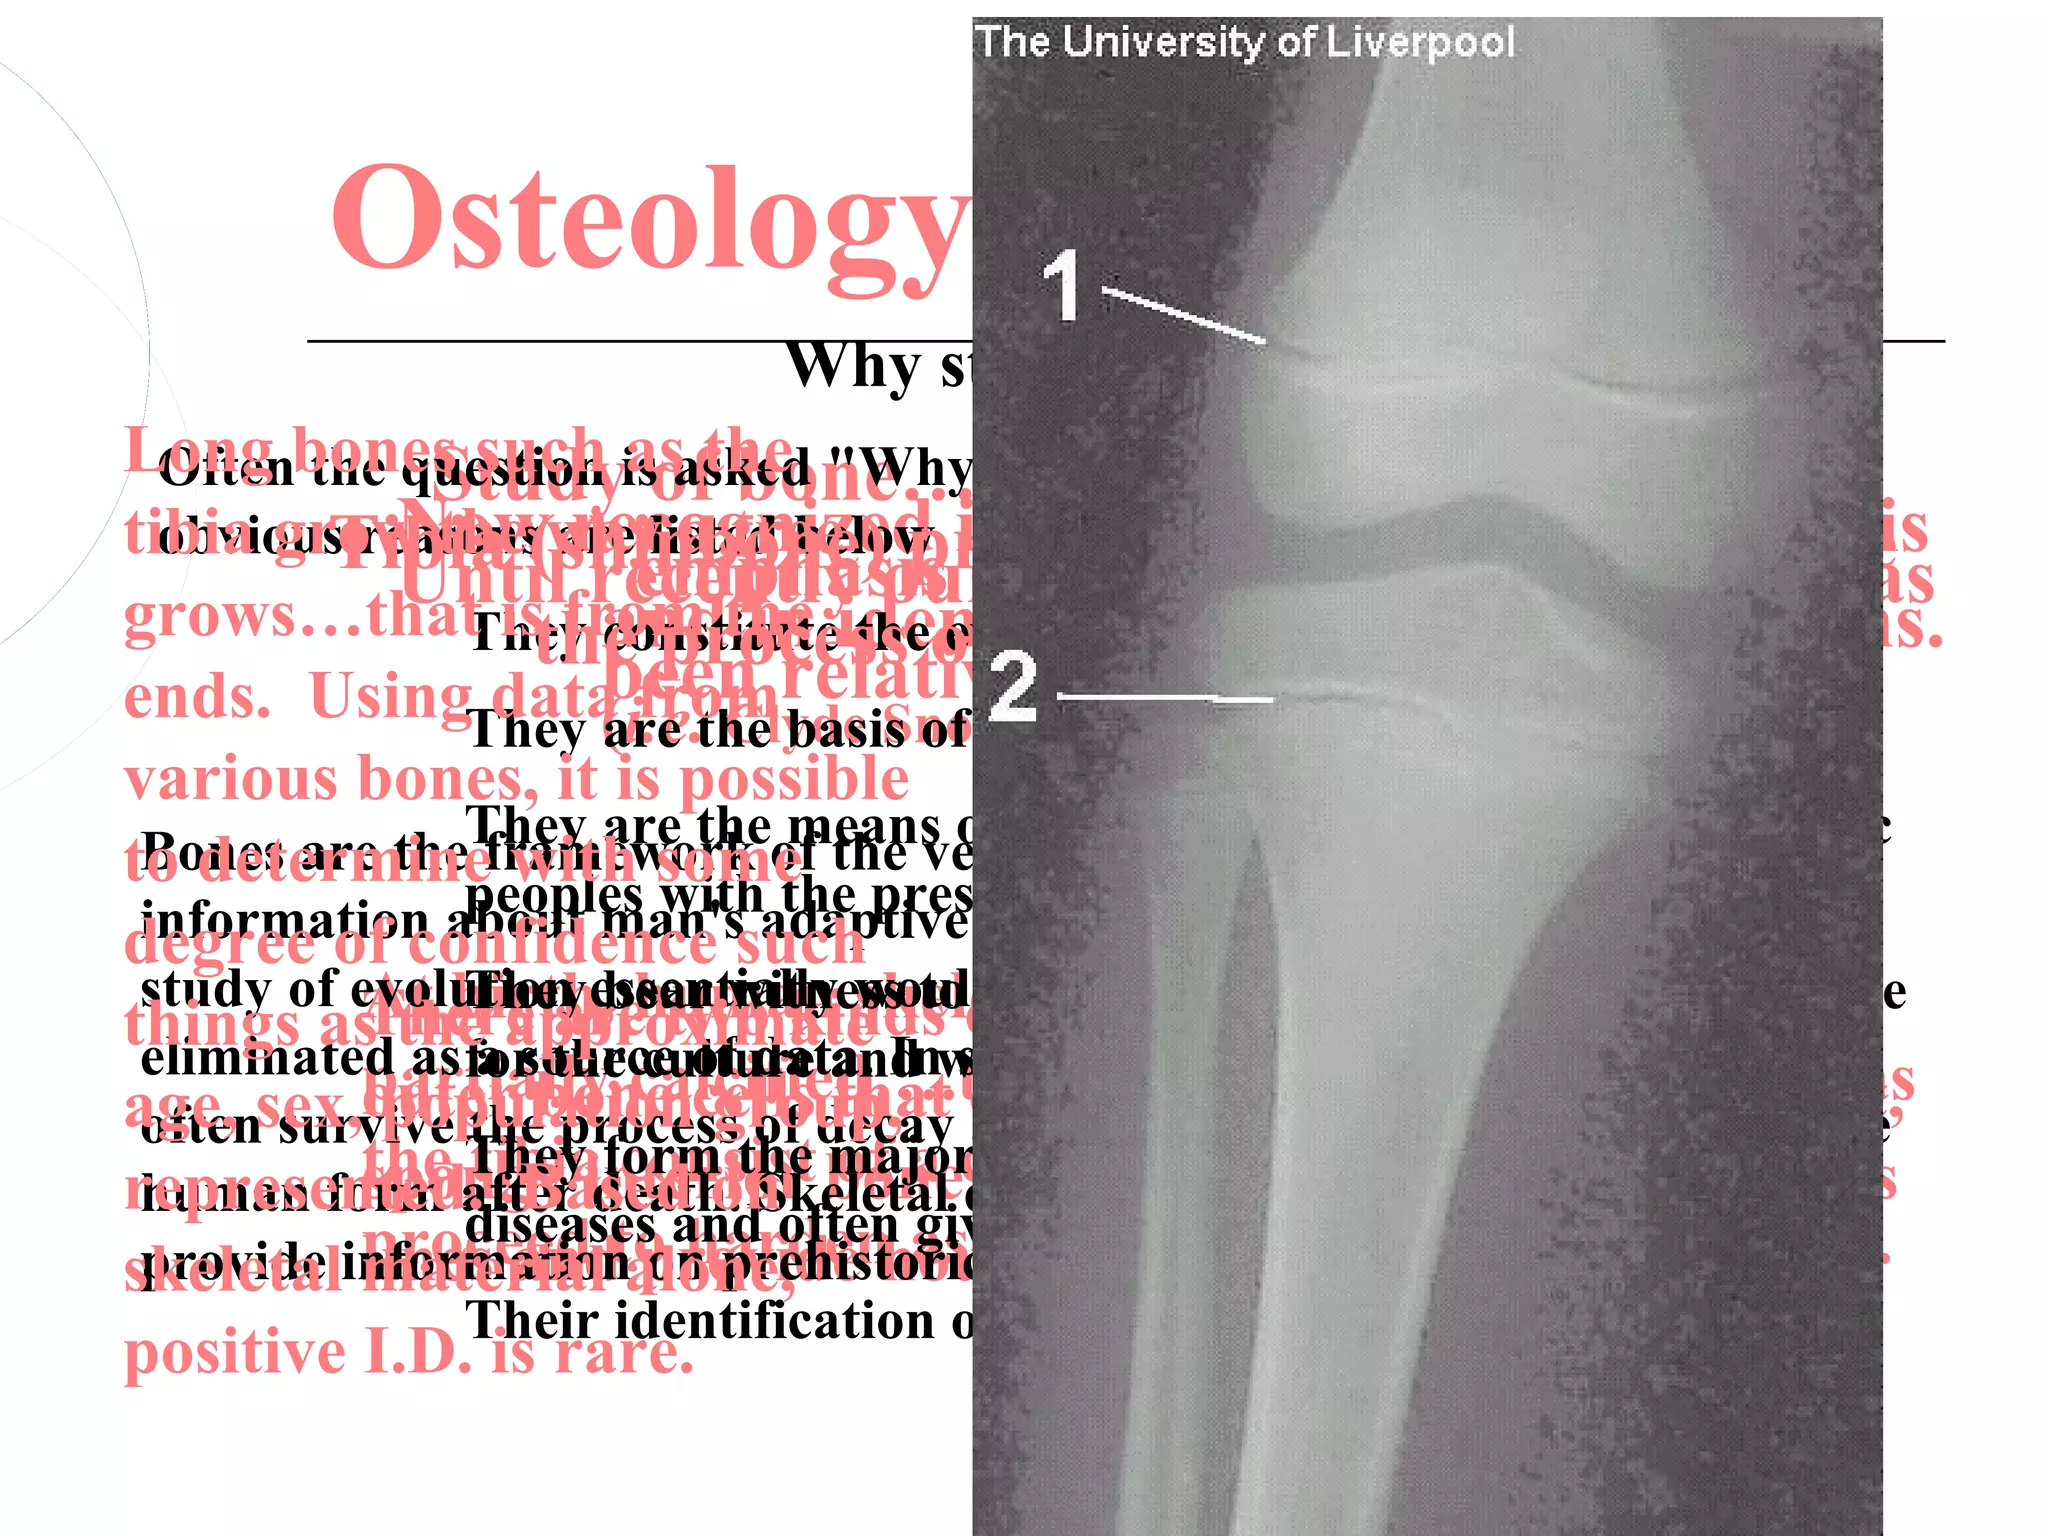

Osteology

Why study bones?

Osteology Why study bones? Long bones such isofthe "Why study bones?" A few of with Often the question as bone….in anthropology the more Study asked Tibia areemphasis inknowledge of osteology has Now recognized prevention of osteoporosis tibia grow the(shinbone) provides a model to illustrate obvious reasons way a tree listed below. Untilfrom the our primates recently on grows…that isthe process of bonefor the study of fossil man. They and in identification of human remains. constitute the evidence development: ends. UsingThey been relatively ignored in prehistory. data from basis of racial Forensic Anthropology) (i.e.the are Clyde Snow and classification various bones, it is possible Bones are theThey are the means of biological comparison of prehistoric to determineframework of the vertebrate body and thus contain much with some present living descendents. peoples withadaptive mechanisms to his environment. The information about man'ssuch the degree of confidence study of evolution essentially would be impossible if bones were evidence At birth,bear witness toof bonevery smallthus give There are two kinds burial patterns and and only They human skeleton is things as theaapproximate Inworld viewcells….essentially hard, eliminated as for the calcified….the skull of theotheris studied. partially culture and summary,oneanswer bones such as source of data. the people that bones age, sex,outer bone cellsdecay overlap and another, and for the often survive the process of that and provide the main evidence a soft, population group, represented. Based onoften a cartilaginous model,of death. the They death.the major whose of information on ancient tibia consist of spongy form Skeletal source also develop along stressand human form after interior boneevidence cellshas the potential to proceed to and diseases harden give clues as to the causes lines and provide as calcification proceeds with age. skeletal material on prehistoric customs marrow. provide informationalone, housing forand diseases. Their identification often helps solve forensic cases. positive I.D. is rare.